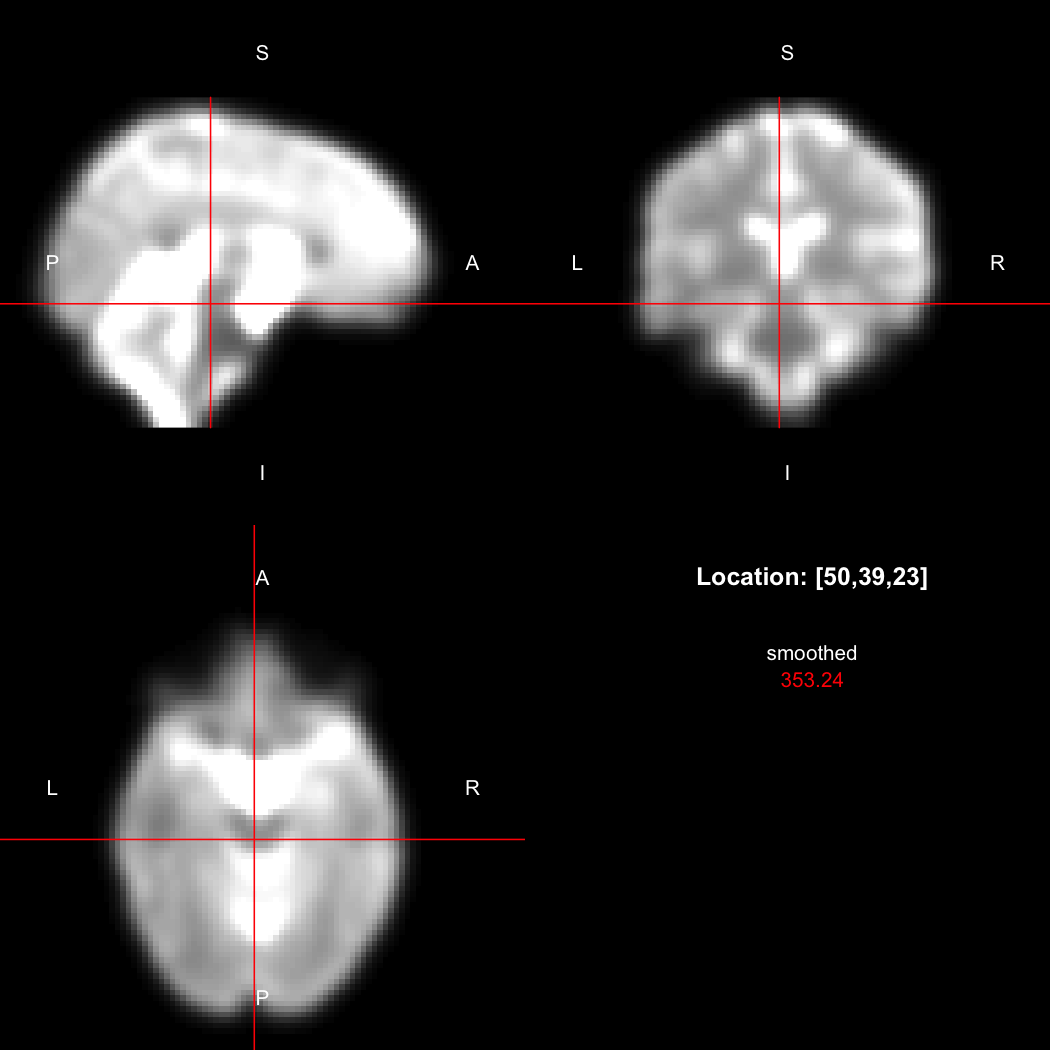

A simple example operation would be to smooth the image with a Gaussian smoothing kernel of standard deviation 4 mm. We can use standard R syntax to perform this operation, return a result, and then show it:

smoothed <- run(smooth_gauss(image, 4))

view(smoothed)

## Setting window to (0, 549.9)

Here, smooth_gauss() requests the smoothing operation,

and run() actually runs the pipeline and returns the

processed image.